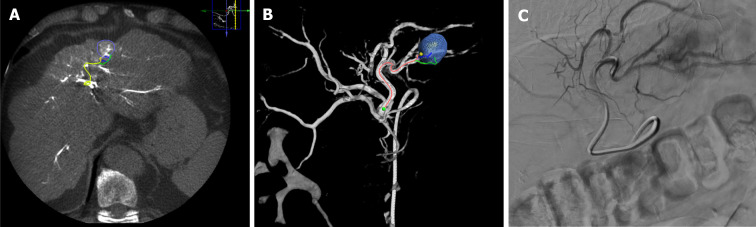

Abstract Image